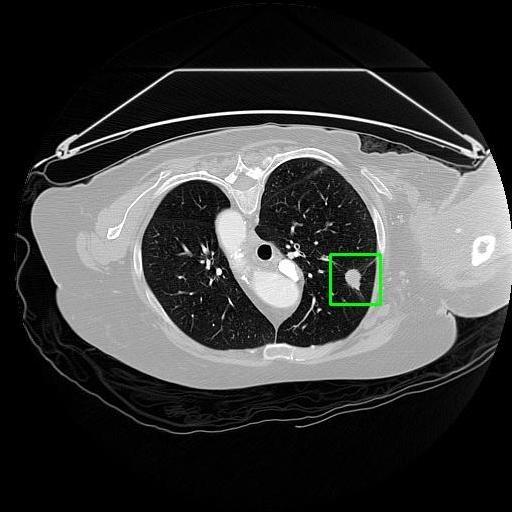

We developed an AI-based system using deep learning models for analyzing lung CT scans to detect and classify pulmonary nodules. We chose the YOLOv11 architecture for its enhanced object detection capability and adapted it specifically for medical imaging, incorporating pixel-level precision and severity classification.

Classification into three severity levels with colored bounding boxes.

Designed a severity classification system that categorizes nodules into null, moderate, and severe using colored bounding boxes, assisting in rapid clinical decision-making.